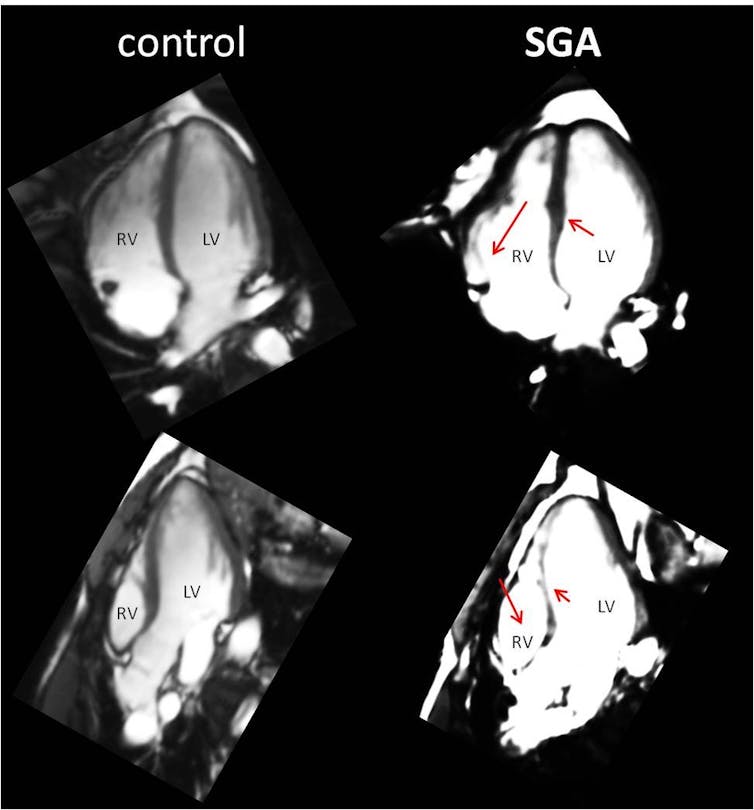

La primera prueba demostró que las personas que habían nacido con bajo peso mantenían cambios en la estructura del corazón en la edad adulta. Su ventrículo derecho tenía una forma diferente.

En este sentido, diversos estudios científicos del grupo de investigación de BCNatal de la Universidad de Barcelona han demostrado que los bebés con bajo peso tienen el corazón más grande e hipertrofiado (con más masa muscular) para así poder hacer circular más sangre y compensar la insuficiente alimentación de la placenta.

Durante más de diez años han estudiado a bebés pequeños para entender cómo su corazón se hipertrofia y adapta a la situación. Estos cambios pueden verse desde que el feto está dentro del útero con una ecografía especial que se llama ecocardiografía fetal.